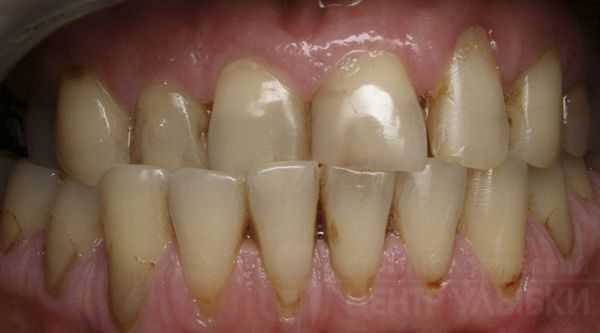

Отсутствие первого нижнего постоянного моляра встречается достаточно часто. При несвоевременном протезировании развиваются деформации зубных рядов, а именно, мезиальный наклон второго нижнего постоянного моляра и супраположение (экструзия) второго верхнего премоляра и первого верхнего постоянного моляра [1].

Согласно классификации ВОЗ (1997), все аномалии положения зубов рассматривают относительно трех взаимно перпендикулярных плоскостей. В трансверзальной плоскости к таким аномалиям относят губно-щечное (вестибулярное) и оральное (небное или язычное) положение зубов, в сагиттальной плоскости - мезиальный и дистальный наклон, в вертикальной плоскости - инфра- и супраположение. Перечисленные аномалии возникают при раннем удалении как молочных, так и постоянных зубов, при неправильном положении зачатков или неправильном положении других зубов [4].